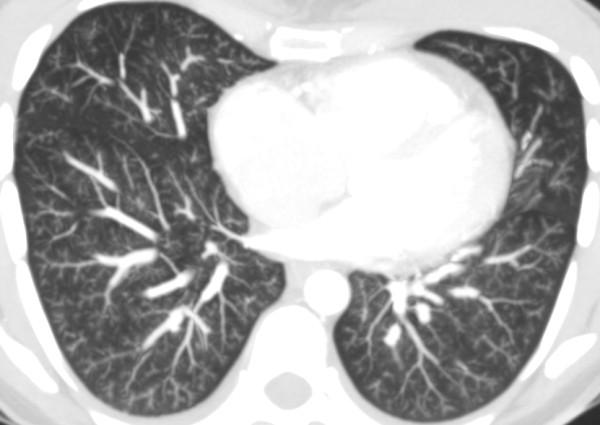

A 28-year-old Caucasian woman with a previous history of pelvic tumor resection two months previously, suggestive of metastatic adenocarcinoma, presented with intense shortness of breath. A computed tomography scan showed signs of acute cor pulmonale and diffuse nodular opacities associated with a tree-in-bud pattern disseminated through her lungs, suggestive of bronchiolitis. Our patient's condition worsened and she underwent a surgical biopsy. Pathologic analysis of the biopsied specimens revealed pulmonary tumor thrombotic microangiopathy. Our patient's tumor evolved from a gastric origin (Krukenberg tumor). She underwent progressive clinical deterioration and died less than 24 hours after the biopsy. None of the cases described previously in the literature had diffuse centrilobular nodular opacities associated with a tree-in-bud pattern disseminated through the lungs, as in our case.

Pulmonary tumor thrombotic microangiopathy should be considered in cancer patients with rapidly progressing dyspnea, chest computed tomography findings compatible with pulmonary hypertension and typical findings of inflammatory bronchiolitis.